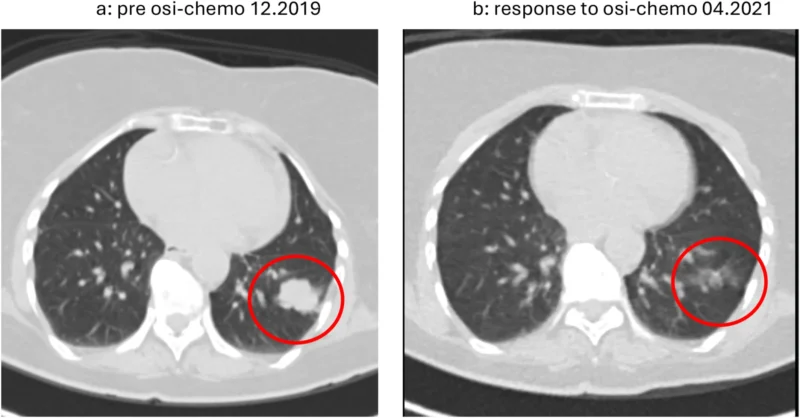

The patient described in this report had metastatic NSCLC harboring an EGFR exon 19 deletion, one of the most common and well-characterized sensitizing mutations. In line with emerging evidence supporting combination strategies, the patient received first-line treatment with osimertinib combined with carboplatin and pemetrexed, reflecting the regimen evaluated in the FLAURA2 trial (Kalofonou et al., 2026).

This approach aims to enhance initial disease control by combining targeted therapy with chemotherapy, potentially delaying the onset of resistance. As expected, the patient initially demonstrated a favorable response, highlighting the continued effectiveness of EGFR-targeted therapy in the frontline setting.

However, as is typical in EGFR-mutant NSCLC, disease progression eventually occurred, prompting further investigation into the underlying resistance mechanisms.